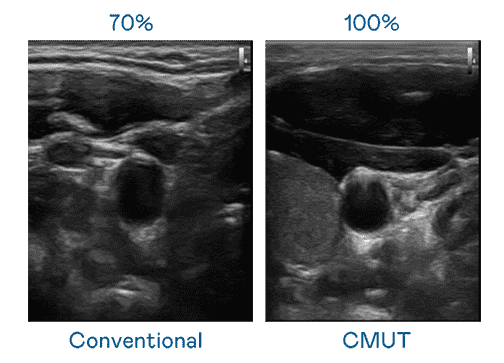

CMUT 技术是一种用电容式微机电元件来产生超音波讯号的技术。。。。与传统 PZT 压电式技术相比,,,CMUT 频宽增加 30%,,,更宽频的超音波讯号让影像解析度大幅提升,,,是实现高影像品质医疗超音波扫描、、、、促进精准医疗发展的关键技术。。。。

大频宽带来超清晰影像

超音波影像的解析度高低,,首先取决于探头能发出的讯号频宽。。。YAXIN111 CMUT 可提供高清晰的超音波讯号,,,,提供高频宽、、、高灵敏度、、、影像纹理细节更高的超音波影像,,,协助医护人员缩短影像判读时间及利用精准的医疗影像进行诊断。。